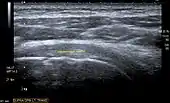

Ultrasound

There are several advantages of ultrasound. It is relatively cheap, does not emit any radiation, is accessible, is capable of visualizing tissue function in real time, and allows the performance of provocative maneuvers in order to replicate the patient’s pain.[26] Those benefits have helped ultrasound become a common initial choice for assessing tendons and soft tissues. Limitations include, for example, the high degree of operator dependence and the inability to define pathologies in bones. One also has to have an extensive anatomical knowledge of the examined region and keep an open mind to normal variations and artifacts created during the scan.[27]

After the introduction of high-frequency transducers in the mid-1980s, ultrasound has become a conventional tool for taking accurate and precise images of the shoulder to support diagnosis.[29][30][31][32][33]

Adequate for the examination are high-resolution, high-frequency transducers with a transmission frequency of 5, 7.5, and 10 MHz. To improve the focus on structures close to the skin an additional "water start-up length" is advisable. During the examination the patient is asked to be seated, the affected arm is then adducted and the elbow is bent to 90 degrees. Slow and cautious passive lateral and/or medial rotations have the effect of being able to visualize different sections of the shoulder. In order to also demonstrate those parts which are hidden under the acromion in the neutral position, a maximum medial rotation with hyperextension behind the back is required.[34]

To avoid the different tendon echogenicities caused by different instrument settings, Middleton compared the tendon’s echogenicity with that of the deltoid muscle, which is still lege artis.[35][36]

Usually the echogenicity compared to the deltoid muscle is homogeneous intensified without dorsal echo extinction. Variability with reduced or intensified[37] echo has also been found in healthy tendons. Bilateral comparison is very helpful when distinguishing and setting boundaries between physiological variants and a possible pathological finding. Degenerative changes at the rotator cuff often are found on both sides of the body.[38] Consequently, unilateral differences rather point to a pathological source and bilateral changes rather to a physiological variation.[36]

In addition, a dynamic examination can help to differentiate between an ultrasound artifact and a real pathology.[39]

To accurately evaluate the echogenicity of an ultrasound, one has to take into account the physical laws of reflection, absorption and dispersion. It is at all times important to acknowledge that the structures in the joint of the shoulder are not aligned in the transversal, coronal or sagittal plane, and that therefore during imaging of the shoulder the transducer head has to be held perpendicularly or parallel to the structures of interest. Otherwise the appearing echogenicity may not be evaluated.[40]

![]() Transversal ultra sonography of the supraspinatus tendon |